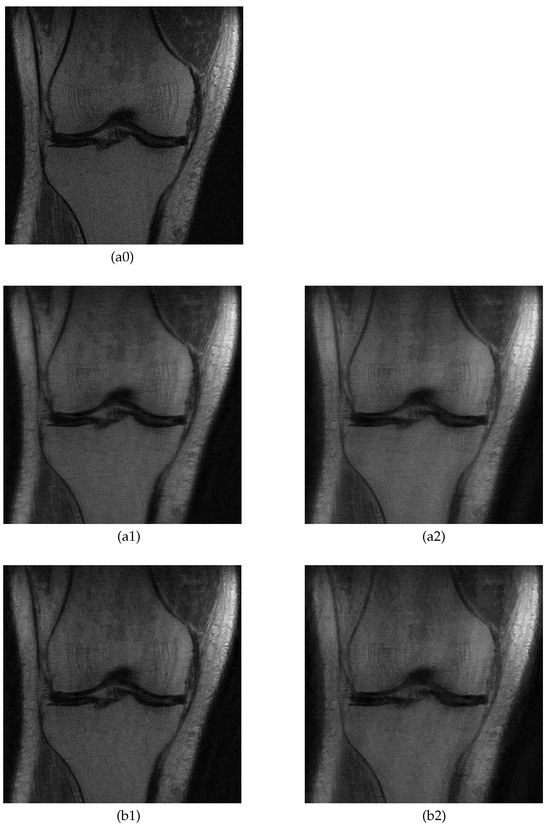

5.2. MRI Image Recovery

| Proposed | TV Method | |||||||

|---|---|---|---|---|---|---|---|---|

| PSNR | SSIM | PSNR | SSIM | |||||

| 4× | 8× | 4× | 8× | 4× | 8× | 4× | 8× | |

| Knee A | 28.5 | 26.4 | 0.657 | 0.570 | 28.2 | 24.5 | 0.615 | 0.538 |

| Knee B | 28.4 | 26.1 | 0.635 | 0.535 | 27.8 | 24.1 | 0.625 | 0.541 |

| Brain A | 27.7 | 24.1 | 0.642 | 0.524 | 26.7 | 22.3 | 0.637 | 0.493 |

| Brain B | 27.7 | 24.6 | 0.668 | 0.494 | 26.8 | 22.7 | 0.644 | 0.474 |